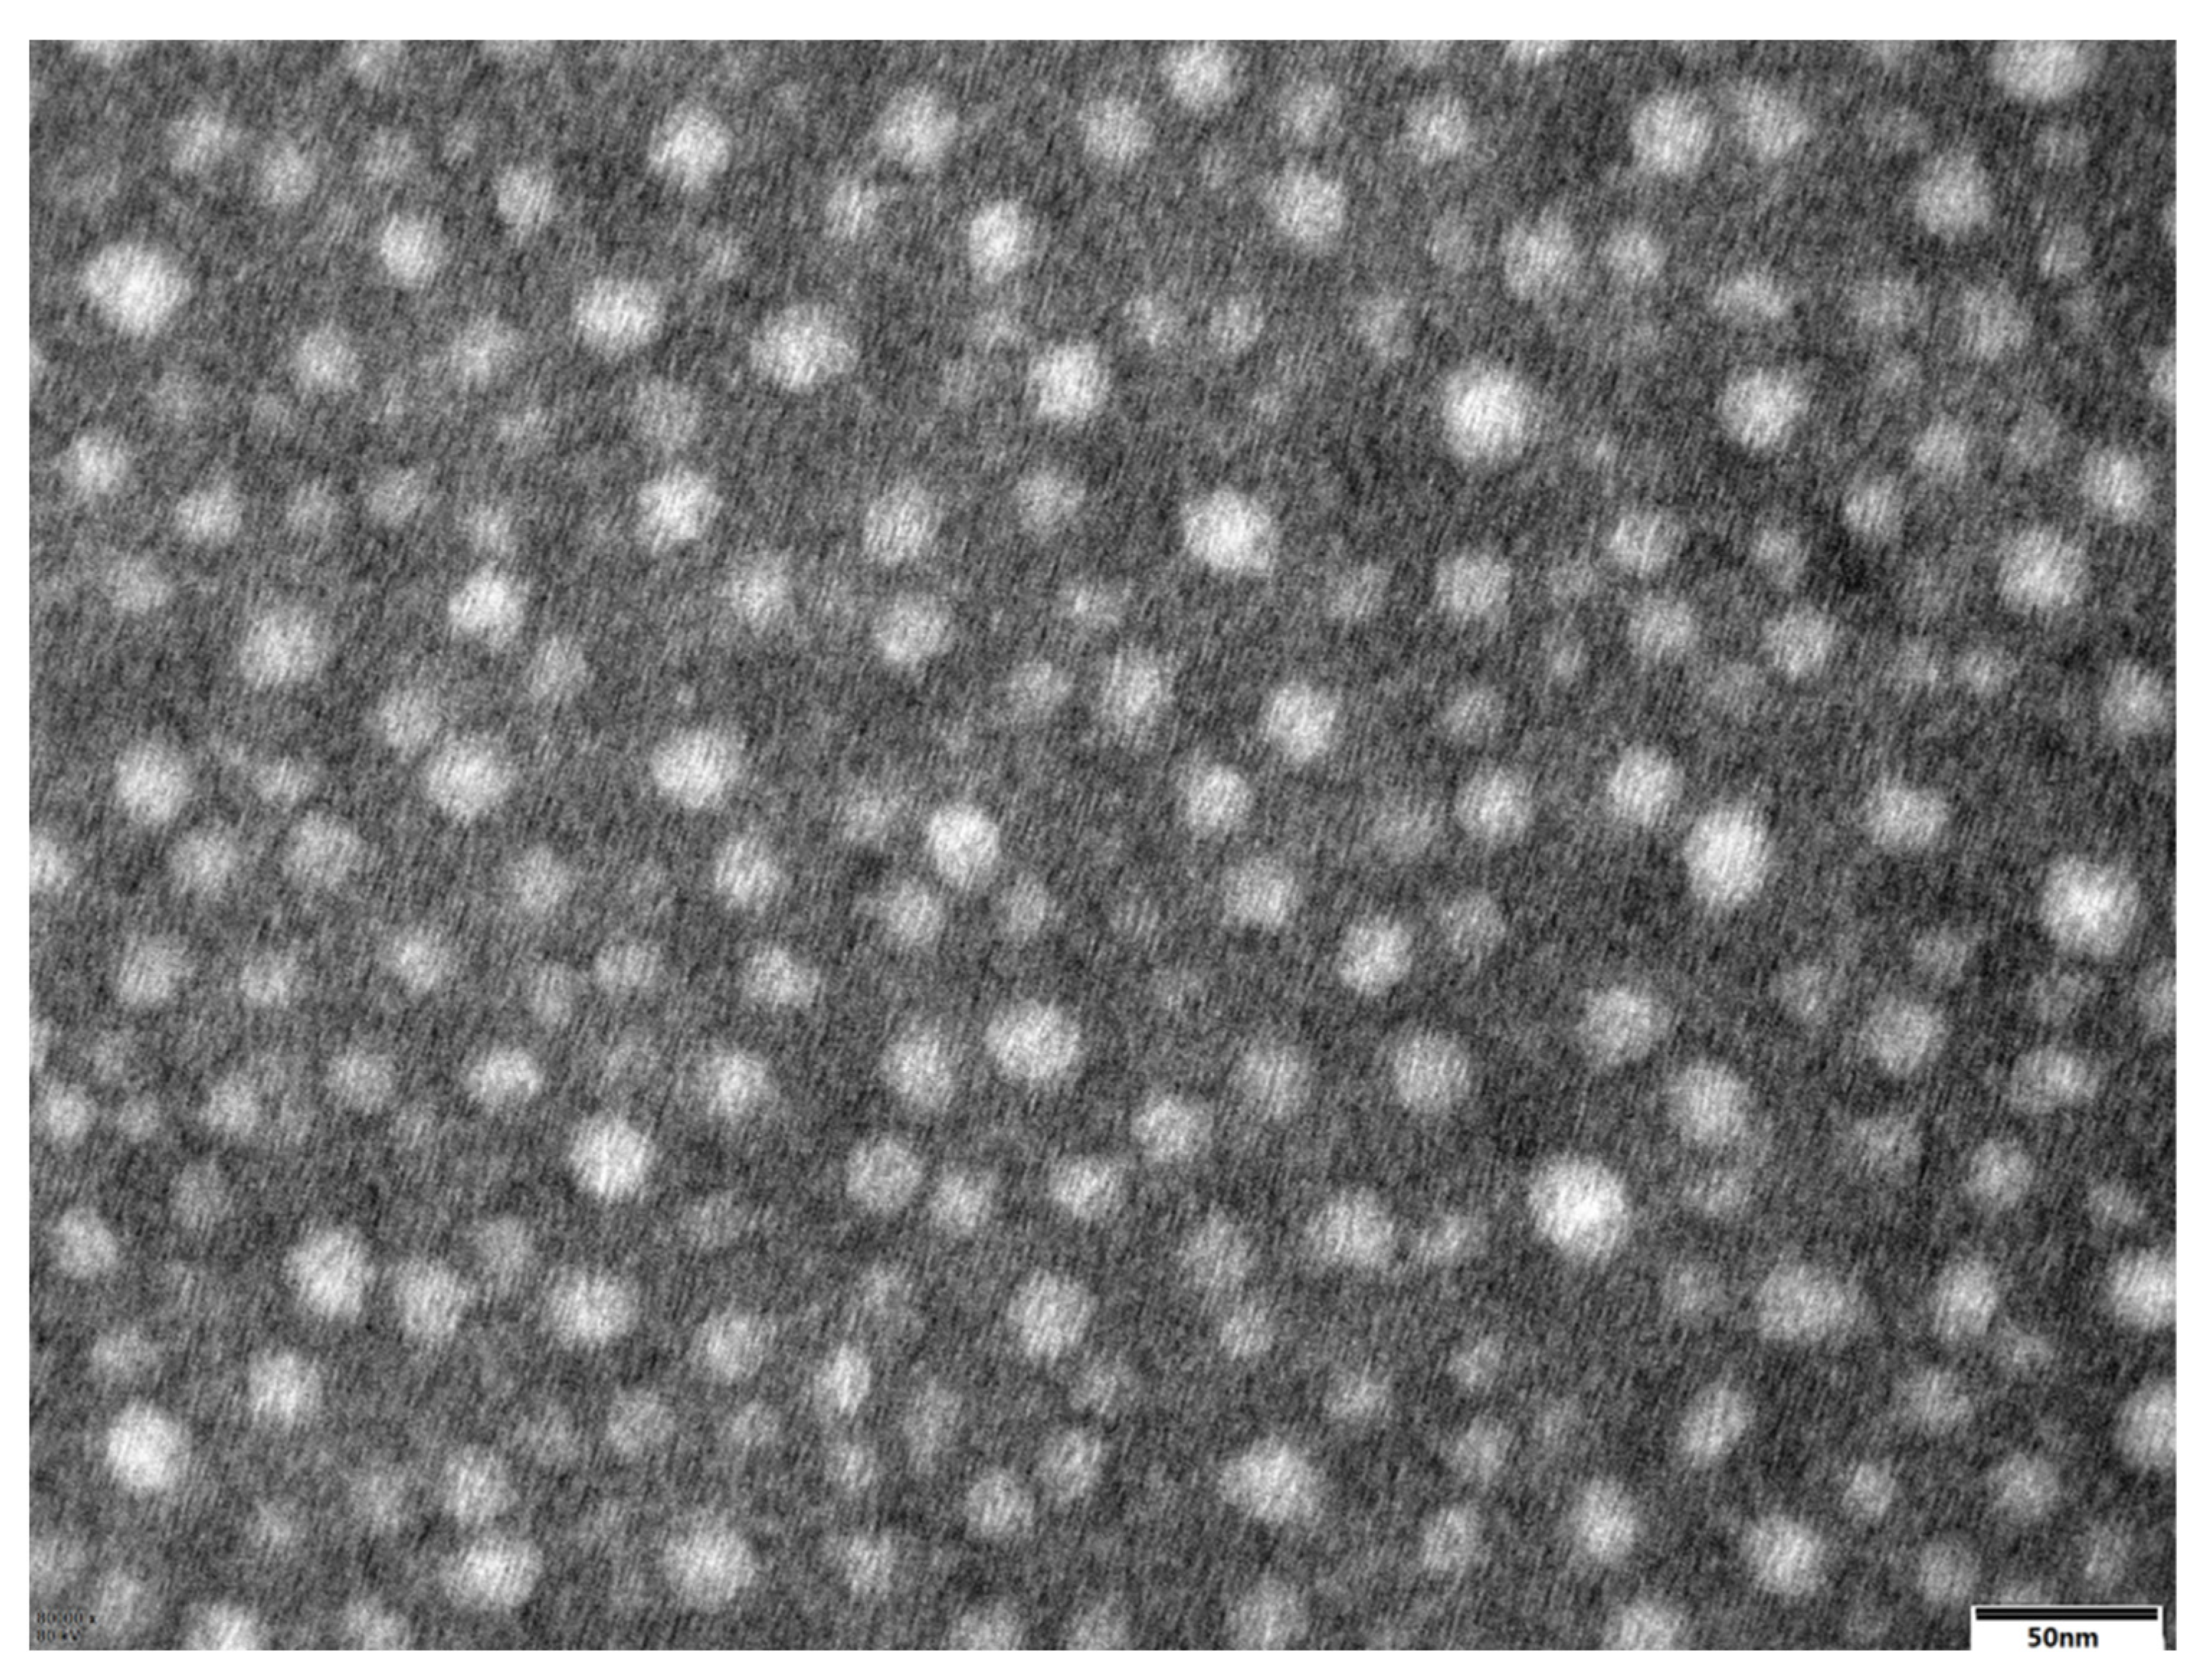

3.3. TEM